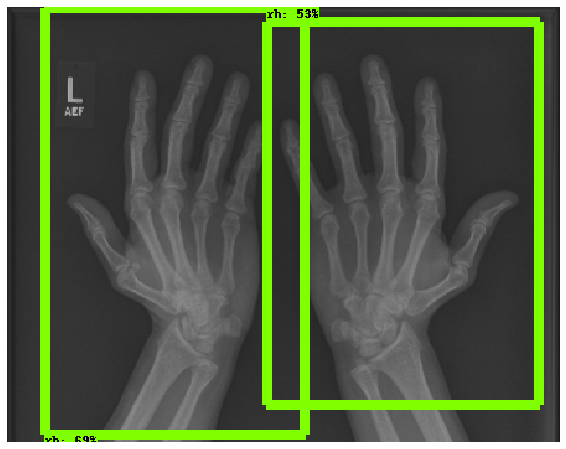

In this work, we focus on a subset of the MURA dataset [17] containing only hand images. In total, we have 5,543 images of 2,018 studies of 1,945 patients. Each study is labeled as negative or positive, where positive means that there was an anomaly diagnosed in this study. There are 521 positive studies, with a total of 1,484 images. Figure 1 shows some examples from the dataset. In summary, our contributions are as follows:

The first step in our pipeline is to detect the X-ray image carrier in the image. To this end, we apply OpenCV’s contour detection using Otsu binarization [14], and retrieve the minimum size bounding box, which does not need to be axis-aligned. This works sufficiently well as long as the majority of the image carrier is within the image (cf. Figure 3). However, the approach might fail for heavily tilted images or those where larger parts of the image carrier reach beyond the image border.

Hand Localization

To further improve the detection of hands, and in particular split the images where two hands are depicted on one image, we manually labeled approximately 150 bounding boxes in the images. Using this small dataset, we fine-tune a pre-trained single shot multibox detector (SSD) [12] with MobileNet as taken from TensorFlow. An exemplary results can be seen in Figure 3.